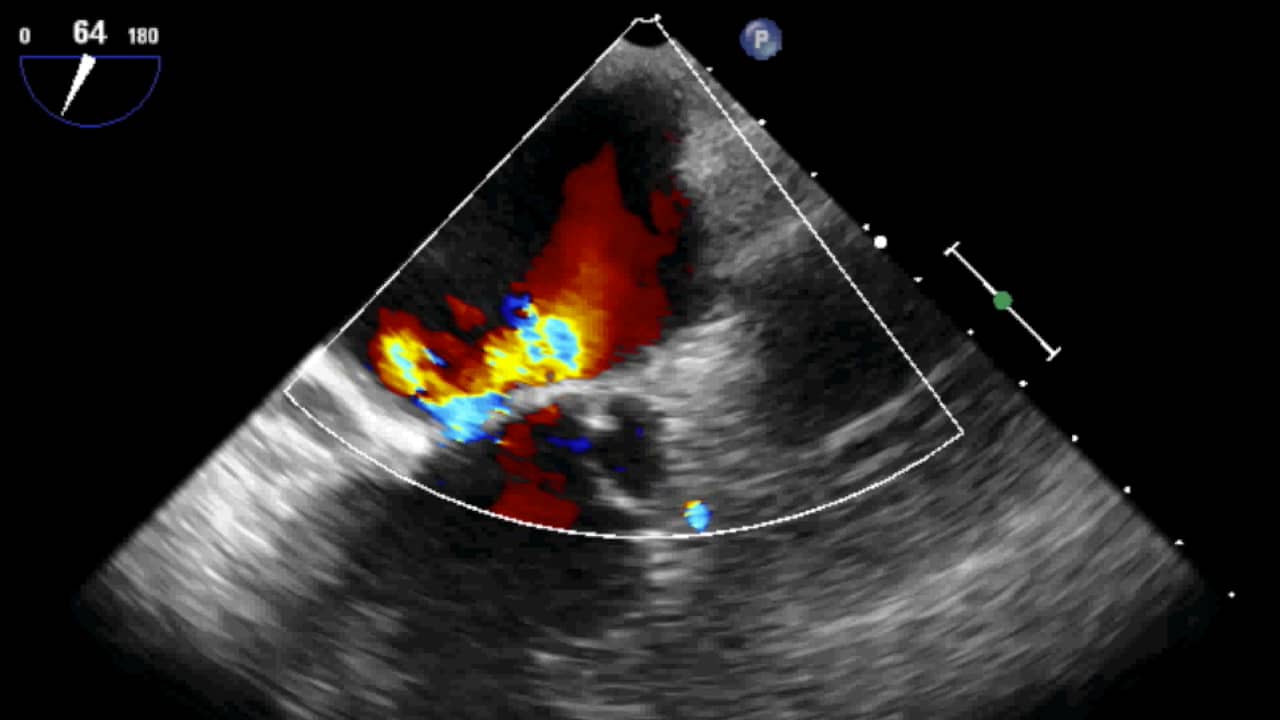

Coanda Effect In Mitral Regurgitation . Moreover, visual assessment of the size of the color flow jet can underestimate mr in eccentric jets that hit the wall of the left. Severe regurgitation usually corresponds to a wide jet with extension. Guidelines suggest that flail leaflet and coanda are specific signs for severe mitral regurgitation. Mri is an accurate method for. Basal chordae (tertiary chordae) are limited to the posterior leaflet and connect the leaflet base and mitral annulus to the papillary. A comprehensive assessment of mitral regurgitation using different echocardiographic techniques provides. A cardiac mri was done to reveal a severe wall hugging eccentric mitral regurgitation jet revealing a coanda effect.

Mitral Regurgitation with Coanda Effect 3/5 Mitral Regurgitation with Coanda Effect In Mitral Regurgitation  Mri is an accurate method for. Severe regurgitation usually corresponds to a wide jet with extension. A comprehensive assessment of mitral regurgitation using different echocardiographic techniques provides. Guidelines suggest that flail leaflet and coanda are specific signs for severe mitral regurgitation. Moreover, visual assessment of the size of the color flow jet can underestimate mr in eccentric jets that hit. Coanda Effect In Mitral Regurgitation.

Coanda effect in a very severe wall hugger mitral regurgitation YouTube Coanda Effect In Mitral Regurgitation  Severe regurgitation usually corresponds to a wide jet with extension. A cardiac mri was done to reveal a severe wall hugging eccentric mitral regurgitation jet revealing a coanda effect. Guidelines suggest that flail leaflet and coanda are specific signs for severe mitral regurgitation. A comprehensive assessment of mitral regurgitation using different echocardiographic techniques provides. Mri is an accurate method for.. Coanda Effect In Mitral Regurgitation.